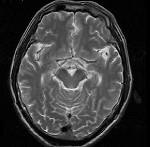

问题 男,头痛7月余,伴左侧面部麻木,疼痛剧烈时伴恶心,无呕吐,请根据所提供图像,选择最可能的诊断()

选项 A.垂体瘤 B.颅咽管瘤 C.生殖细胞瘤 D.脑膜瘤 E.胶质瘤

答案 B